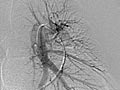

La angiografía pulmonar es una radiografía que utiliza un tinte especial y una cámara (fluoroscopia) para tomar imágenes del flujo sanguíneo en los vasos sanguíneos de los pulmones.

La angiografía pulmonar se usa para evaluar las arterias que van a los pulmones (arterias pulmonares) y los vasos sanguíneos en los pulmones. También puede detectar el estrechamiento o la obstrucción de un vaso sanguíneo que reduce o detiene el flujo de sangre.

Una vez que se haya colocado el catéter, se inyecta el material de contraste a través de él. Es posible que se le pida que inhale y contenga la respiración durante varios segundos. Se tomarán varias imágenes radiográficas, una tras otra. Estas estarán disponibles de inmediato para que su médico pueda observarlas. Debe permanecer muy quieto para que las imágenes sean nítidas. A veces, solo se estudia un pulmón, o se puede repetir el proceso más de una vez para cada pulmón.

La angiografía pulmonar es una radiografía que utiliza un tinte especial y una cámara (fluoroscopia) para tomar imágenes del flujo sanguíneo en los vasos sanguíneos de los pulmones. Es posible que su médico le comunique algunos resultados inmediatamente después de la prueba. Por lo general, los resultados completos están listos el mismo día.